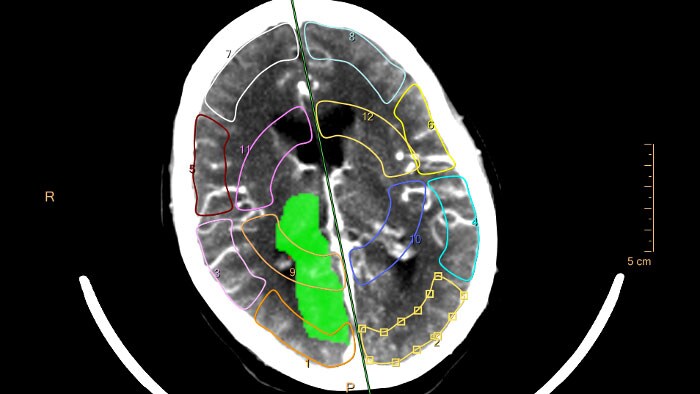

Perfusão cerebral por TC

Calcula e apresenta mapas resumidos do fluxo reduzido que oferecem informações clínicas importantes em pacientes com derrames agudos para ajudar no planeamento do tratamento.